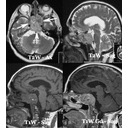

tumor.jpg